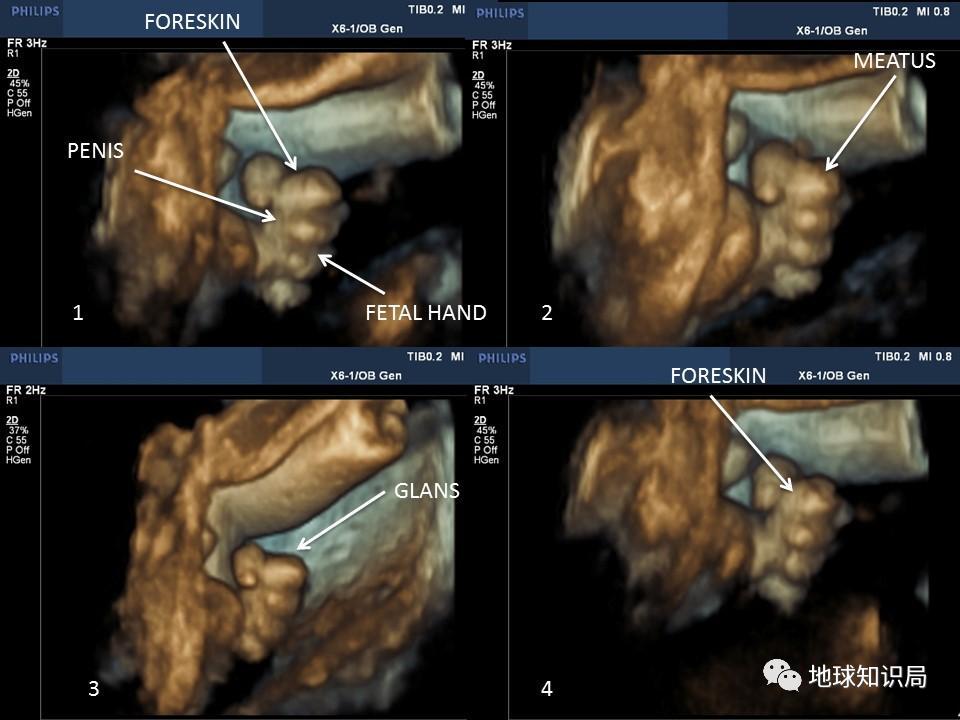

毕竟,目前观察到年龄最小有*慰自**行为的个体,是子宫内 妊娠24周的胎儿。